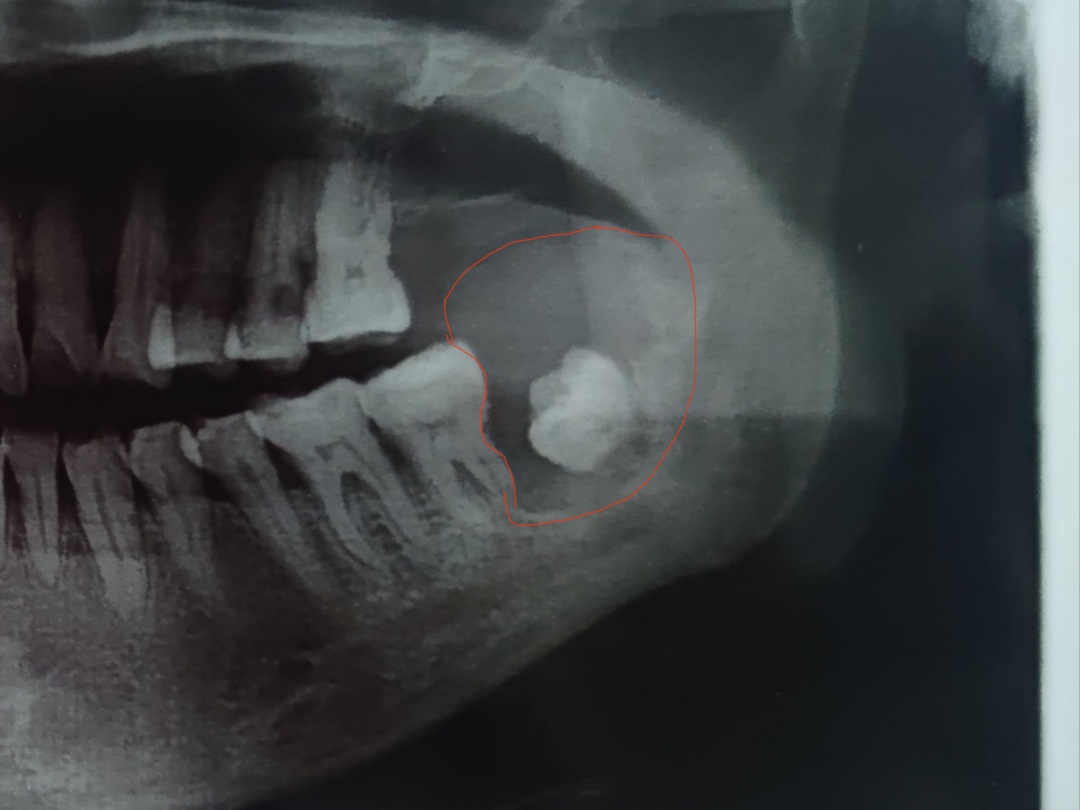

7月7日,刘女士来我院口腔一科就医,经副主任高永志检查发现,刘女士因为智齿多年埋伏于下颌骨内,未萌出, 从而导致牙源性下颌骨巨大肿瘤,同时通过口腔曲面断层扫描可见肿瘤已侵犯至下牙槽神经管。高永志向主任王金山汇报病例后,两人制定了详细的手术治疗计划,经与患者充分沟通后,将收患者入院治疗。

7月8日,患者完善各项检查后,于全麻下行“左下颌骨肿物切除术”,经过一个多小时的手术,成功将患者口内的肿瘤切除,并且最大限度地保护了神经和血管。术后患者术区无出血、下唇无麻木、恢复了吞咽和发音功能。患者对我院口腔一科的技术水平赞不绝口,连连夸赞道:我选择齐一附属,口腔一科就诊是最明智的选择。